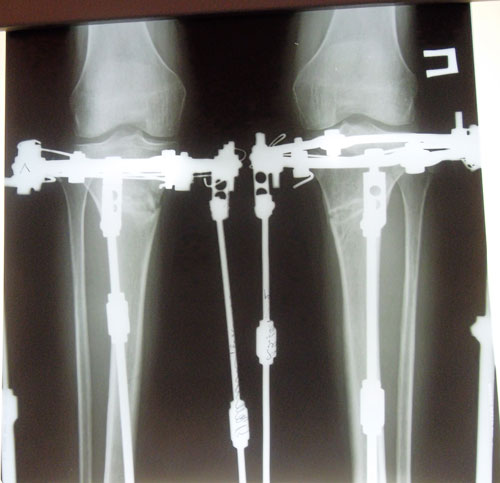

Дата снятие аппаратов 24.10.2013г.

Срок лечения 104 дня.